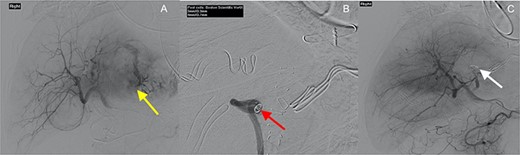

(A) macroscopic specimen demonstrating slices through a haemorrhagic lesion with normal liver parenchyma; (B) images demonstrating liver with intact architecture (black arrow) with HCC (white arrow) and (C) patchy nuclear staining with arginase-1 immunohistochemical stain.

Histopathological assessment revealed an 85-mm moderately differentiated HCC with evidence of vascular invasion that was completely excised with a 20-mm clear margin [TNM Staging (AJCC 8th edition): pT2] (Fig. 3). The patient’s recovery post-procedure was routine with transfer back to the rural hospital 13 days post-liver resection.